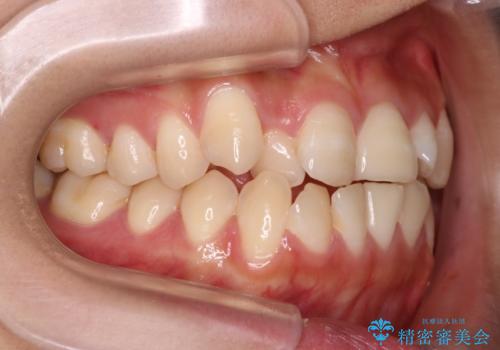

- 前歯のガタガタを主訴に来院されました。

インビザラインも提案しましたが、装着時間を確実に確保できるか不安ということもありワイヤー矯正を希望されました。